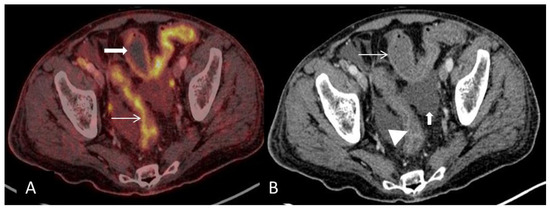

(A) Coronal PET and CT fused image demonstrates multifocal segmental pathological FDG-uptake in small-and large bowel loops. Circumferential mural pathological FDG-uptake in the large bowel (arrows). (B) Coronal CT shows engorgement of the vasa recta (circle) and mural enhancement of the large bowel (arrow). Ascites is present on the surface of the liver. Engorgement of the vasa recta is due to increased blood-flow in small arteries of inflamed bowel segments and has been reported as the most consistent extraintestinal finding in acute GIT-GVHD [2].